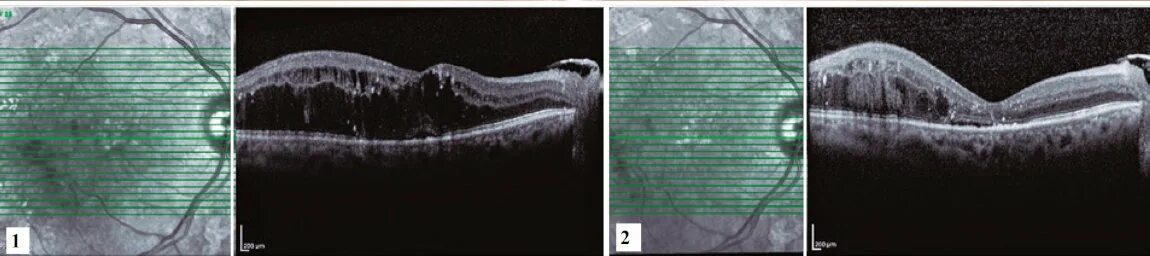

Озурдекс имплантат для интравитреального